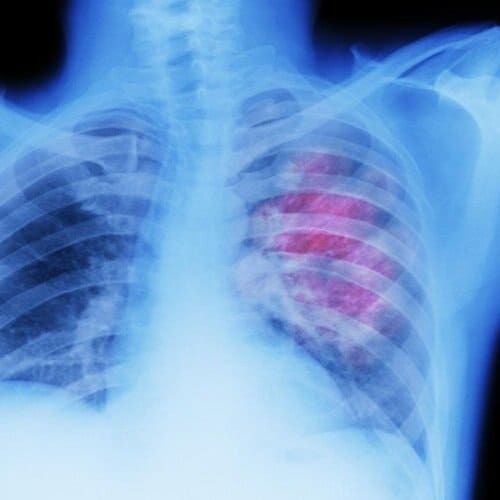

Our collaborator at Charles River, Julia Schüler, PhD DVM wrote a blog post titled Finally, Reliable Drug Screening Platforms for Lung Cancer Biomarkers, discussing the impact of 3D Tumor Models in screening patient-derived NSCLC tumors.